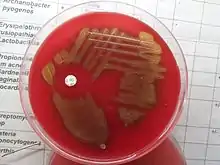

Culture

- Les pneumocoques sont aéro-anaérobie facultatifs, ne possèdent pas de catalase (l'absence de catalase entraîne en culture une accumulation d'eau oxygénée qui tue le germe et c'est sans doute par l'apport de catalase que l'adjonction de sang est la plus utile).

- Développement favorisé par la présence de liquides organiques (sang).

- Leurs colonies sont transparentes, en gouttelettes de rosée, lisses (S) pour les pneumocoques virulents capsulés. La perte de la capsule entraîne à la fois la perte de virulence et la modification de la colonie qui devient rugueuse (R). Les colonies sont parfois très muqueuses chez les souches fortement capsulées, de plus ou moins 1 mm, dont le centre s'affaisse après 2 à 3 jours (autolyse).

- Sur gélose au sang frais, il n'y a pas de vraie lyse des globules rouges mais éventuellement un léger verdissement autour de la colonie (hémolyse de type alpha : transformation de l'hémoglobine en biliverdine).

- Sur gélose chocolat + polyvitex, l'hydrolyse de l'hémoglobine en biliverdine se traduit par une zone d'éclaircissement jaune-verdâtre autour des colonies.

- Ils entraînent un léger trouble du bouillon de culture.

Pour les différencier des streptocoques auxquels ils sont très apparentés, on parle de Streptococcus pneumoniae dans certaines nomenclatures, on se fonde sur les caractères suivants :

- lyse rapide de la bile à 5 % (ou sels biliaires) ;

- inhibition par l'optochine (éthylhydrocupréine) dont on peut imprégner un disque de papier buvard à déposer sur la gélose ;